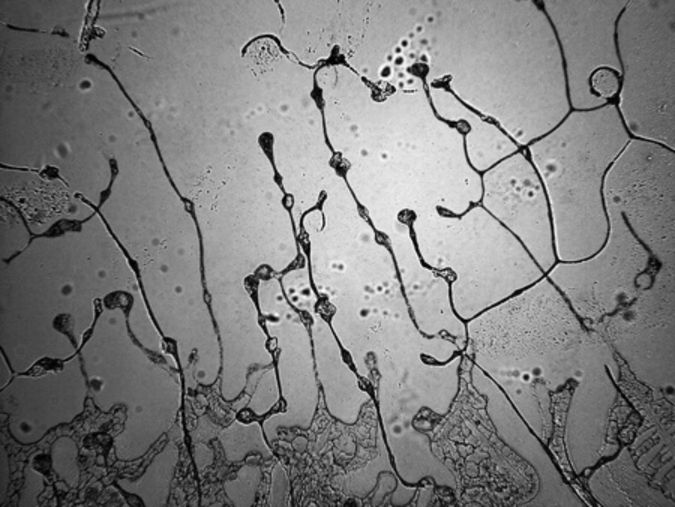

Płyny ustrojowe są niezbędne do funkcjonowania organizmuPłyny ustrojowe są niezbędne do funkcjonowania organizmu

Źródło zdjęć: © 123rf